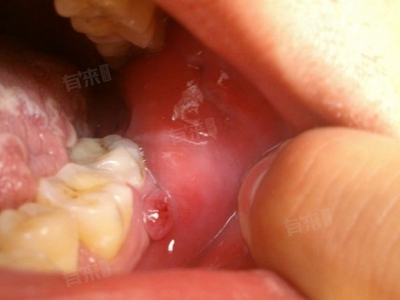

5、智齿脱落:智齿属于恒牙,若因龋坏、阻生等拔除,或自然脱落,因智齿对咬合功能影响较小,且无替代牙胚,无需特殊处理。但若出现疼痛、出血等异常症状,需及时就医检查处理。